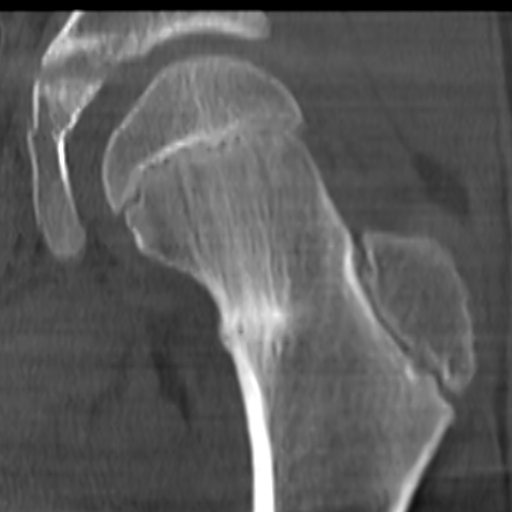

КТ: Перелом шейки бедра под нагрузкой

Используются 4 метода на разных этапах диагностики и лечения [6][10]

1. Рентгенография,

3. МРТ (имеет наивысшую чувствительность и специфичность [6]